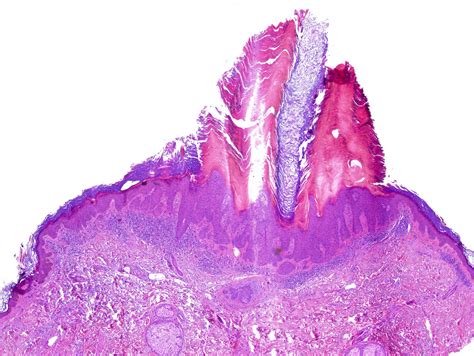

Hypertrophic actinic keratosis is a subtype of actinic keratosis (AK) that is characterized by excessive keratin production, leading to a thickened, elevated, and crusty lesion. Unlike the flat or slightly raised texture of typical actinic keratosis, the hypertrophic variant feels physically hard, rough, and may even resemble a small horn or a wart-like growth. Because these lesions accumulate a thick layer of scales, they are often more palpable and visually distinct against the surrounding skin.

• hypertrophic actinic keratosis histology

• hypertrophic actinic keratosis pathology outlines